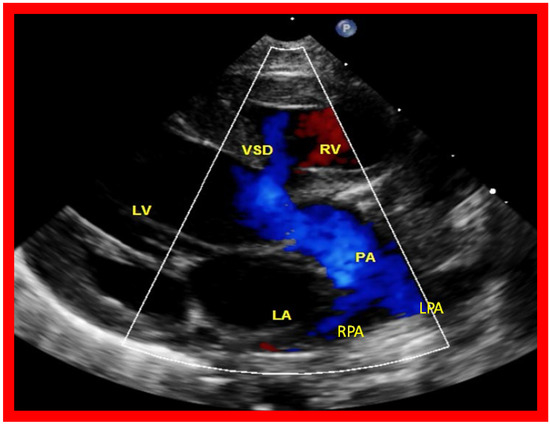

Then, the ventricular septum is evaluated; the ventricular septum is intact in most Type Ia cases. In children with Type I (normally related great arteries), the VSD supplies the pulmonary blood flow (Figure 10) while in patients with Type II (transposition of the great arteries) the VSD allows the blood to flow into the systemic circuit (Figure 11; Figure 12). In Type I patients, the VSD is demonstrated by 2D (Figure 10A), and the left to right shunt across it by color (Figure 10B), pulsed and CW (Figure 10C) Doppler signals. The interrogation of the RV outflow tract and PA region should be performed; recording the peak Doppler flow velocity across the RV outflow tract and the pulmonary valve is helpful in identifying obstruction across these sites. The Doppler data from the VSD and RV outflow tract are also helpful in the estimating of PA pressures. In Type I babies, the 2D size of the VSD and the peak Doppler flow velocity across it are useful in quantifying the size of the VSD (Figure 10). The higher the VSD Doppler flow velocity, the smaller the defect. However, in patients with pulmonary hypertension or severe infundibular or valvar pulmonary stenosis, the VSD Doppler velocities are not reflective of the size of the VSD. Barring these exceptions, RV and PA systolic pressure may be estimated using a modified Bernoulli equation (RV/PA systolic pressure = systolic blood pressure – 4V2).

Figure 10. Selected video frames from parasternal long axis views of a patient with tricuspid atresia with normally related great arteries demonstrating an enlarged left atrium (LA) and left ventricle (LV), a small right ventricle (RV) and a moderate sized defect (VSD) (thick arrow) on 2D (A) and color flow (B) imaging. The turbulent flow (B), with a Doppler flow velocity of 2.91 m/s by continuous wave Doppler (C) across the VSD, suggests some restriction of the VSD. Ao, Aorta; PA, pulmonary artery. Reproduced from Reference [29].

Applsci 11 09472 g010

Figure 12. A selected video frame from a parasternal long axis view with color flow mapping of another patient with tricuspid atresia and transposition of the great arteries demonstrating the left atrium (LA), left ventricle (LV), a small right ventricle (RV) and a moderate sized ventricular septal defect (VSD). The vessel coming off the LV bifurcates into right (RPA) and left (LPA) pulmonary arteries. Reproduced from Reference [29]. PA, pulmonary artery.

Applsci 11 09472 g012